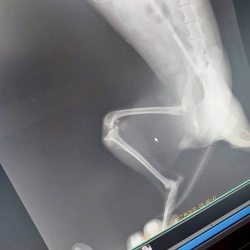

10歳OVER のラキをはじめ、若くても病気を放置されていた為に病状が悪化した状態で保護された子、獣医さんに記録更新と言われた18本もの抜歯をした子、体力がない為に入退院を何度も繰り返す子、他にもたくさん・・・